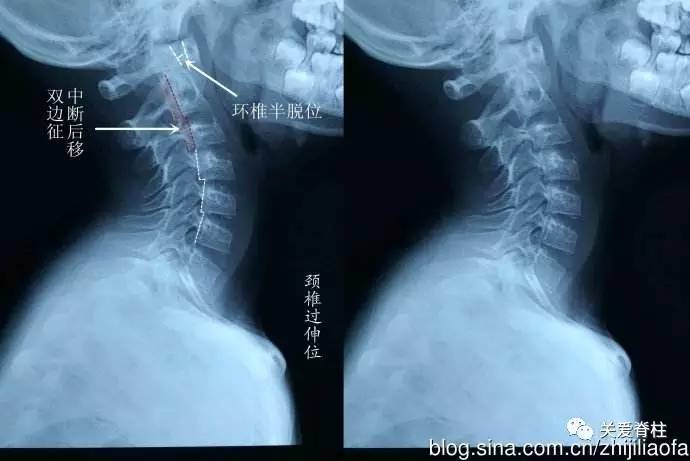

儿童颈椎骨突出图片

儿童颈椎x光片

儿童颈椎影像

儿童颈椎x线